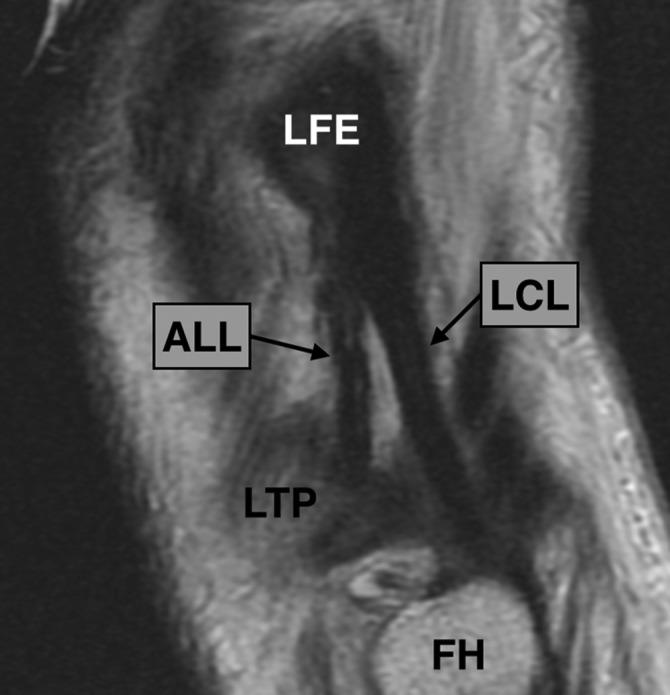

The ALL was clearly observed in all dissected knees and MRI scans. It originated anterior and distal to the LCL, close to the lateral epycondile center, and showed an anteroinferior path toward the tibia, inserting between the Gerdy tubercle and the fibular head, around 5 mm under the lateral plateau. The ρ values tended to increase together for all studied variables between the 2 methods, and all were statistically significant, except for thickness (P = .077). Bland-Altman plots showed a tendency toward a reduction of ALL thickness and width by MRI compared with anatomic dissection.

所有解剖膝关节和 MRI 扫描中均清楚地观察到 ALL。它起源于 LCL 的前侧和远端,靠近外侧髁中心,呈前下向胫骨方向走行,插入 Gerdy 结节和腓骨头之间,位于外侧平台下方约 5mm 处。两种方法之间,所有研究变量的 ρ 值均呈增加趋势,除厚度外(P=0.077),均具有统计学意义。Bland-Altman 图显示,与解剖学检查相比,MRI 扫描中 ALL 的厚度和宽度呈减小趋势。